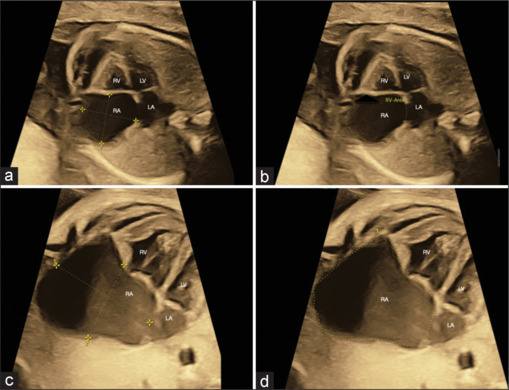

右心房动脉瘤(RAA)是一种罕见的先天性心脏畸形,可起源于心房或附件的游离壁。我们报告一个使用三维/四维时空图像相关胎儿超声心动图及其产后随访的产前诊断RAA的病例。

Right atrial aneurysm (RAA) is a rare congenital heart malformation that can originate from the free wall of the atrium or the appendage. We report a case of prenatally diagnosed RAA imaged using three-dimensional/four-dimensional spatiotemporal image correlation fetal echocardiography and its postnatal follow-up.